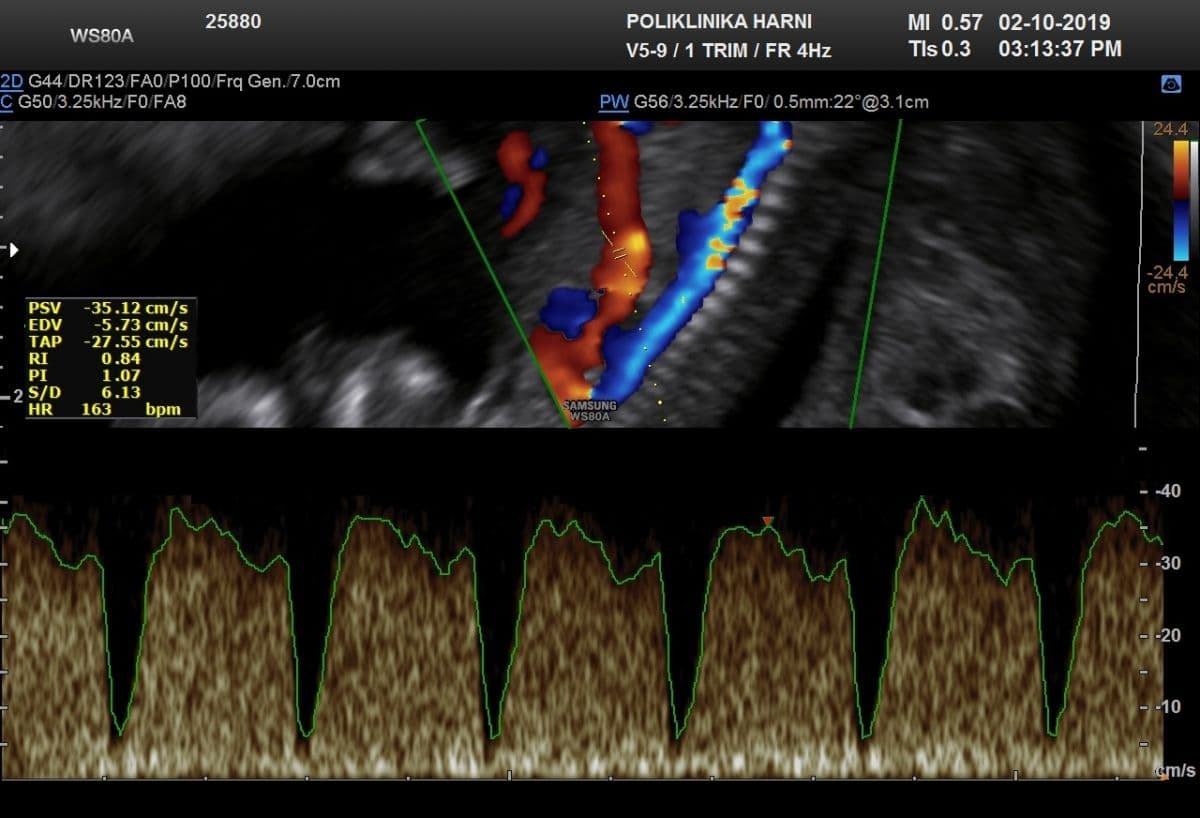

Pri pregledu obojenim Dopplerom između 11. - 14. tjedna trudnoće se u oko 80% fetusa trisomijom 21 otkriva nulti / zero flow" ili obrnuti protok / reverse flow tijekom atrijske kontrakcije u duktusu venosusu. Duktus venozus krvna je žila koja povezuje pupčanu venu i desnu pretklijetku fetalnog srca, a u slučaju trisomije, najvjerojatnije zbog pratećih srčanih grešaka, tijekom kontrakcije pretklijetke protok kroz ovu krvnu žilu se ne bilježi ili je negativan. Otuda je pregled protoka kroz duktus venozus tehnikom obojenog Dopplera, uz opisane soft markere sastavni dio svakog ozbiljnijeg traganja za ultrazvučnim biljezima kromosomopatija.

Ranije je opisano da se tehnika obojenog Doplera primjenjuje i ranije, u okviru otkrivanja odsutnosti ili reverznog protoka krvi kroz duktus venozus ili na srčanoj valvuli između desne pretklijetke i klijetke / trikuspidalna regurgitacija. U 70-90% fetusa s kromosomskim abnormalnostima se pri ovom pregledu između 11.-14. tjedna trudnoće u tim krvnim žilama nalazi inverzan protok, pa je mjerenje protoka kroz duktus venozus tehnikom obojenog Doplera sastavni dio svakog ozbiljenijeg traganja za ultrazvučnim biljezima kromosomopatija.